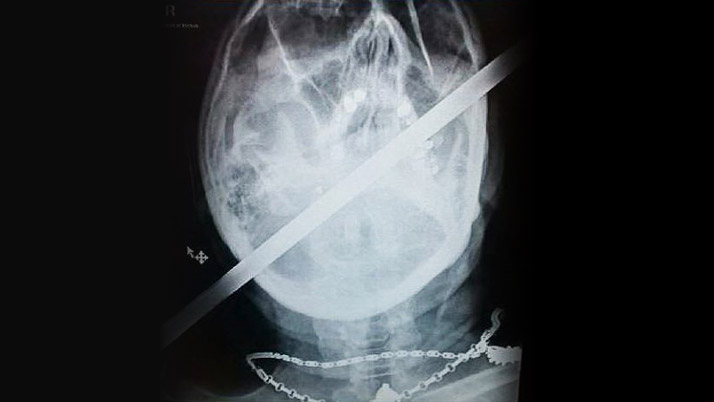

KAFASINA DEMİR ÇUBUK SAPLANAN ADAMIN MUCİZE KURTULUŞU